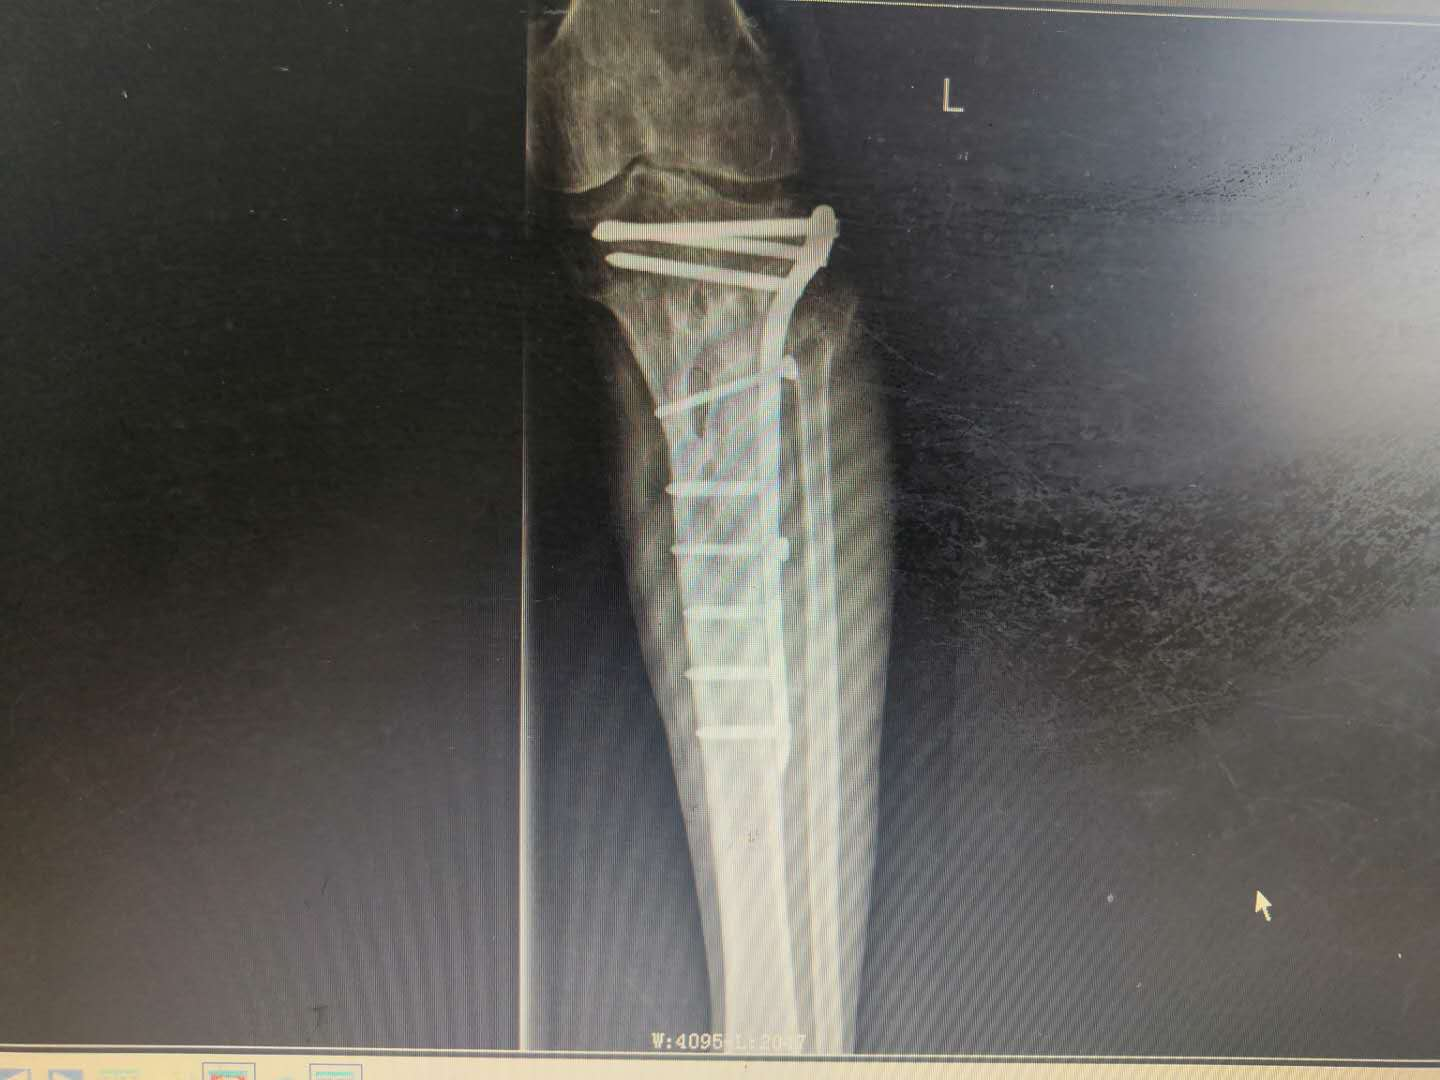

患   者:阳某,男,58岁。

主   诉:因左胫骨骨折术后伤口流脓5年,入院治疗。

现病史:自诉5年前因车祸致左小腿上段疼痛伴活动受限,在当地医院诊断为“左胫骨上段粉碎性骨折”,并行骨折切开复位内固定术,术后伤口未完全愈合,持续流出脓性液体,予伤口间断换药处理,伤口可愈合,但间断出现破溃口,其内流出脓液,现就诊于我院。

专科检查:左小腿中上段前外侧可见长约15cm纵行手术疤痕,周围部分皮肤色素沉着,可见两处皮肤溃口,挤压有脓性分泌物流出,皮下可扪及条状硬物,轻压痛,无异常活动,肢端血运感觉尚可。

辅助检查:血生化检查:血常规示白细胞12.35*109/L,血沉40mm/h,CRP正常,余未见明显异常。

影像资料:

1598324150170814.png1598324150719209.png

诊       断:

右胫骨上段慢性骨髓炎;右胫腓骨陈旧性骨折伴胫骨骨折术后内固定物滞留。

专家指导

针对此病例诊断及治疗方案,杨述华教授指导如下:

此病例诊断正确。

治疗时,需要将钢板取掉,如果骨头没长好,可以采用外固定防止再次骨折。在窦道口采用麻醉科硬膜外导管进行美蓝染色,顺着美蓝方向彻底清除慢性窦道。之后可以采取VSD负压引流,用抗生素冲洗伤口,再进行皮肤缝合;也可以直接缝合皮肤,缝合间距大一些。